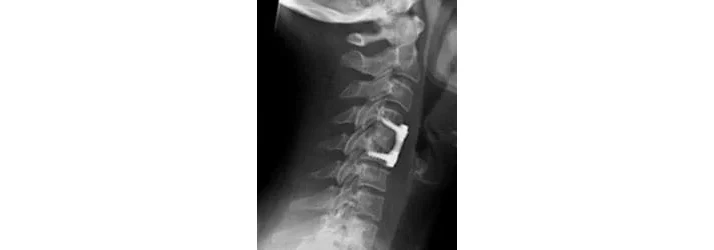

The goal of the most common type of spinal surgery is to stabilize a damaged area by fusing the segments. Essentially, making two bones one. This is done several different ways but the end result is the same: limited mobility, months of recovery, and a 50% chance the symptoms return weeks, months, or years later. This occurrence is called Failed Back Surgery Syndrome.

Now after a surgical fusion takes place, the mobility of that area is decreased. As you heal, you begin to regain some of that mobility back but the issue is how that is being done. The different regions of the spine have varying amounts of mobility in all the different directions. For example, it's very common to be able to bend your neck to the side around 45 degrees. You have 7 cervical vertebrae and a couple of the thoracic vertebrae get in on this movement as well. (We'll say that the first two thoracic are the only two involved for the sake of the example.) That gives us 9 moving segments to create that 45 degrees - giving us +/- 5 degrees at each segment. As long as all the segments are in the proper position, 5 degrees is not stressful to a singular motion segment. Let's say two vertebrae are fused. What ends up happening is that the segments above and below the fusion will be the two areas that make up for the lack of movement due to the fusion - causing an extreme amount of stress to those two "healthy" joints. Over time, this additional wear and tear will cause weakening, instability, misaligment, nerve pressure (subluxation) and eventually the dis-ease process (which will affect what ever sensory, motor, organ, and/or gland signals that are sent through that nerve). If this additional wear and tear is not offset, future surgery is commonly recommended - which will compound the issue.

So the question becomes, how can chiropractic help? A specific chiropractic adjustment will offset the wear and tear created by the extra stresses of the changed movement pattern. Keeping these vertebrae in line, limiting or eliminating the nerve interference, will allow your body to continue to function at its peak capacity. Great care should always be used when adjusting the spine but adjusting a patient that has had surgery requires a skilled doctor to ensure the proper use of stabilization, a correct line of drive, and proper patient positioning to limit any stresses to surgical areas. The Gonstead Technique shines in this area because of being the most biomechanically complete approach to adjusting as well as using instrumentation to specifically identify areas that are experiencing nerve interference. This is why Gonstead Chiropractors have so much success with difficult cases.